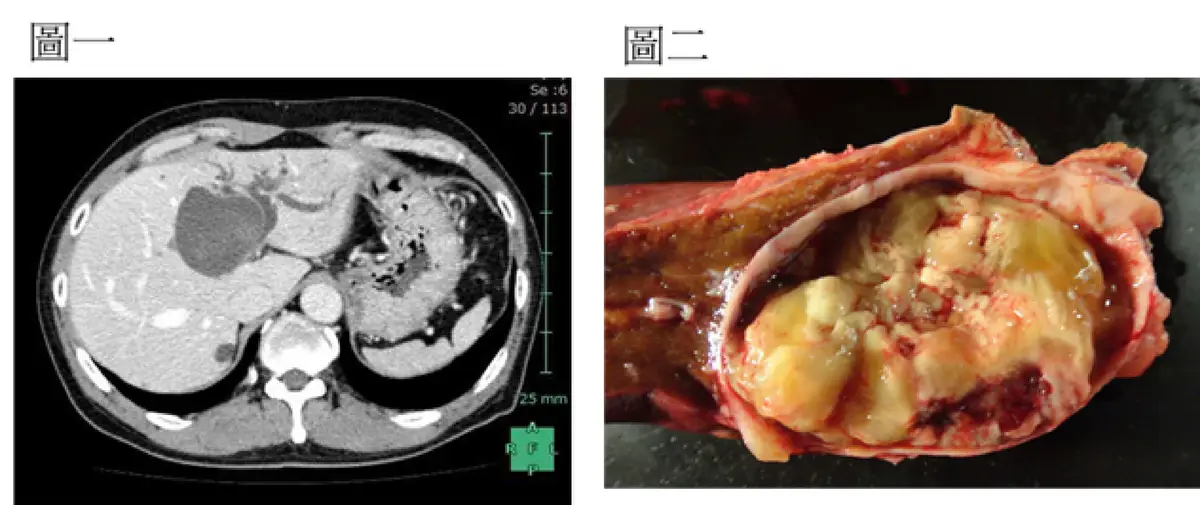

59 歲男性因腹脹求診,電腦斷層檢查如圖一,該病人接受腹腔鏡切除手術,手術標本如圖二,下列何者正確?

本題考查肝臟囊性腫瘤的影像判讀與臨床病理對照。圖一為腹部電腦斷層(CT),圖二為手術標本,須綜合兩者特徵判斷腫瘤位置、性質及其對膽道系統的影響。

圖一(CT 橫切面): 圖中可見肝臟左葉(畫面左側)有一顆巨大、邊界清楚的囊性病灶,密度不均勻,以低密度(接近液體)為主,伴有局部內部分隔或稍高密度區域,符合囊性腫瘤(cystic neoplasm)表現。肝右葉未見明顯異常。病灶並非位於尾狀葉(caudate lobe),而是明顯位於左肝葉。腫瘤體積龐大,可對左肝管(left hepatic duct)造成壓迫及阻塞。

圖二(手術切除標本): 切開後可見腫瘤並非全實心,而是一囊性腫瘤,內部充滿黃白色黏液樣物質(mucinous content)及多房性分隔(multilocular septae),局部可見出血(hemorrhagic areas)。整體外觀符合**膽道囊腺瘤(biliary cystadenoma)**的巨觀病理特徵,並非膿瘍(abscess)亦非純實心腫瘤(solid mass)。